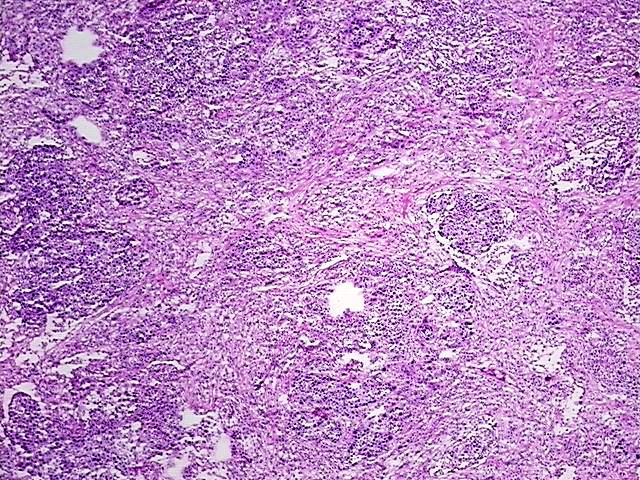

4x Image